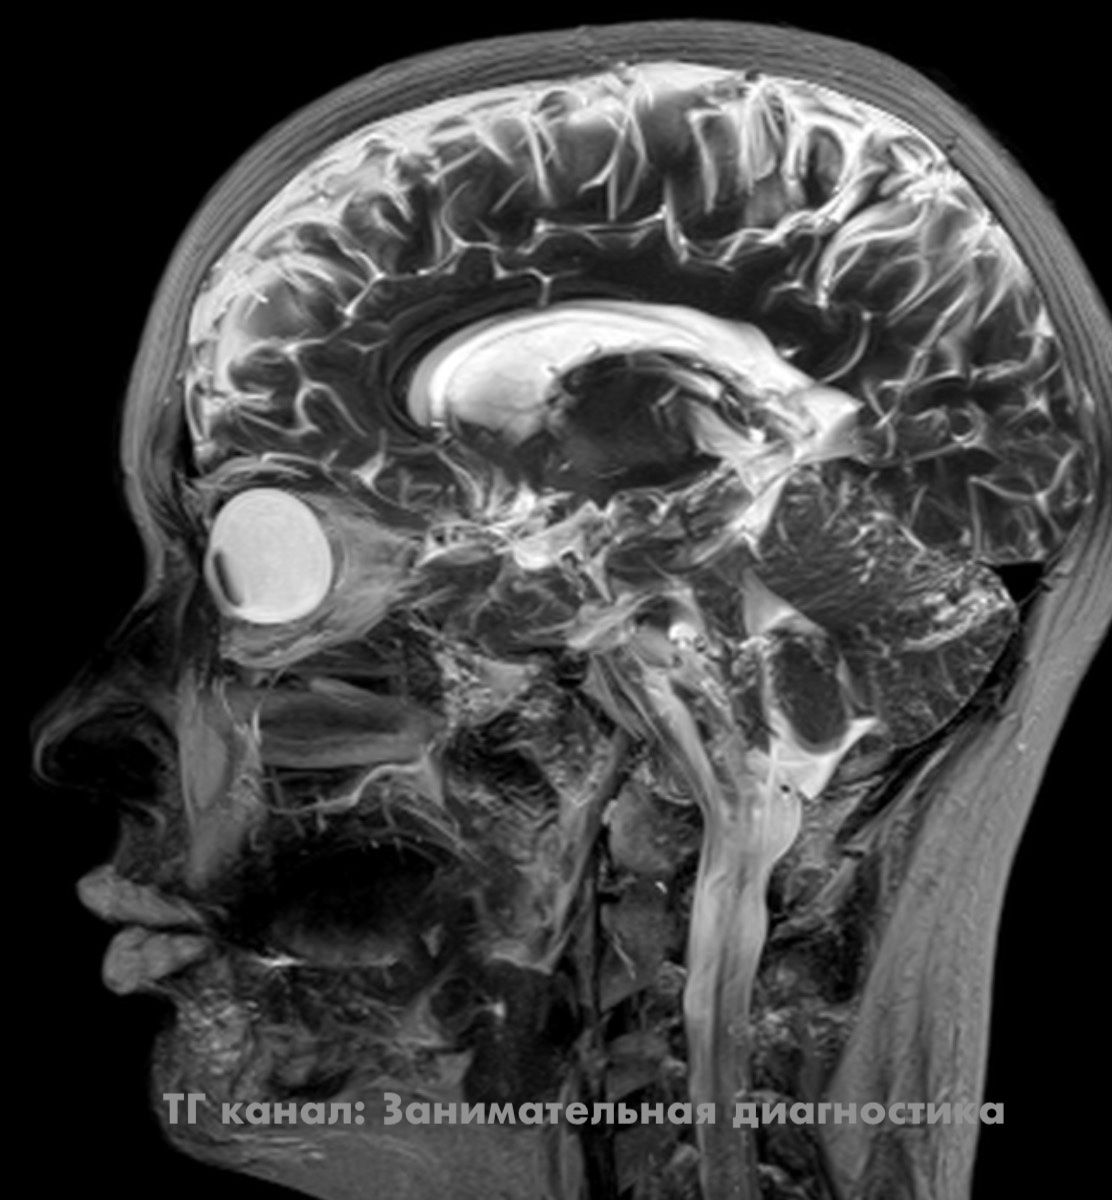

Каких нибудь 20 лет назад доктор, анализируя МРТ, мог бы впасть в ступор, пытаясь понять что такое с губами. Но мы то в наше время живём и понимаем - это просто молодая особа сделала в губы инъекции филлера (гиалуроновой кислоты). Красота! Коллега предположил, что такими губами, наверное, хорошо играть на губной гармошке. P.S. тёмные линии в толще губ на боковых срезах - это мышцы. Также хорошо видно зубы. *** Читать ещё на Дзен:

Каких нибудь 20 лет назад доктор, анализируя МРТ, мог бы впасть в ступор, пытаясь понять что такое с губами.

Но мы то в наше время живём и понимаем - это просто молодая особа сделала в губы инъекции филлера (гиалуроновой кислоты).

P.S. тёмные линии в толще губ на боковых срезах - это мышцы. Также хорошо видно зубы.